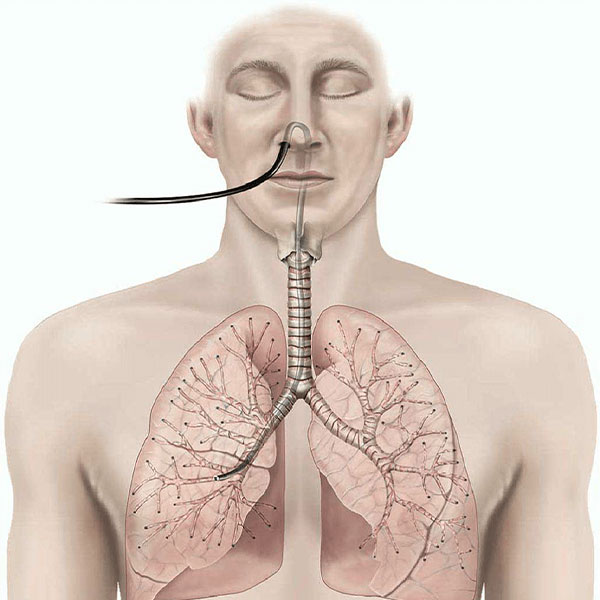

Bronchoscopy

Bronchoscopy is a medical procedure used to examine the airways, diagnose lung conditions, and perform treatments.

EBUS

EBUS (Endobronchial Ultrasound) is a minimally invasive procedure for diagnosing lung diseases using ultrasound guidance.